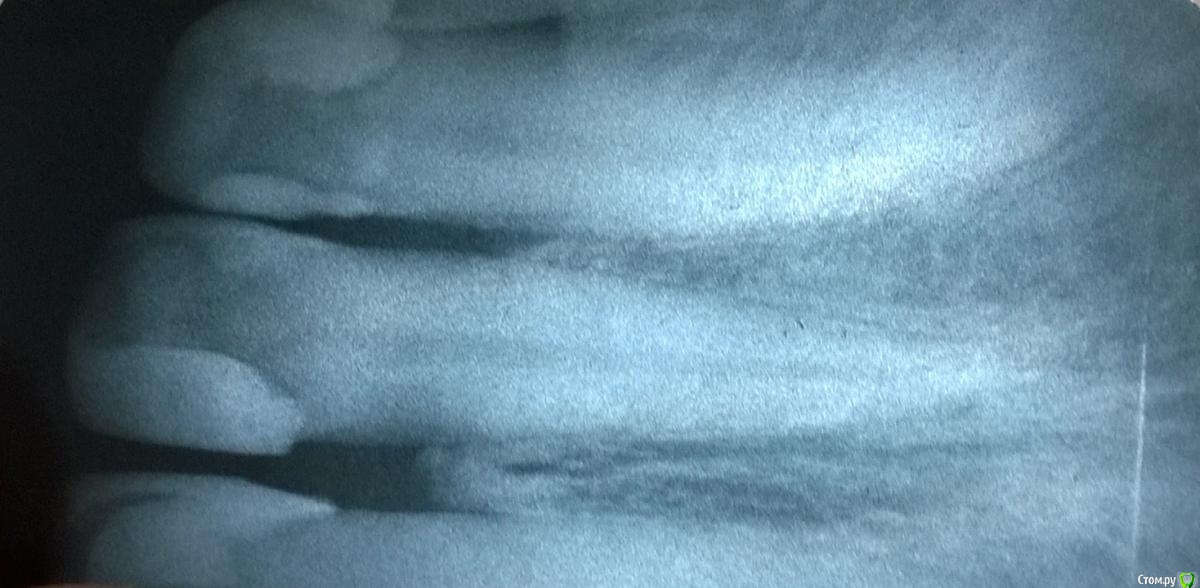

Создать аккаунт